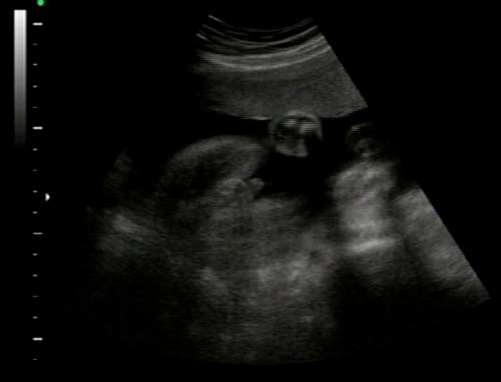

Hi all. thanks for your help! been told its a boy at 27weeks. I am interested in what you have to say.

All boy! Congrats :)

Yep, it's a boy!

Boy!